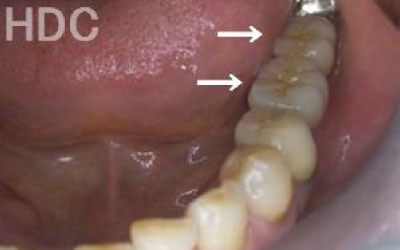

2 歯が傾いてくる、落ちてくる

歯は互いに支え合い、バランスを保っています。そのため、歯が抜けると支えがなくなり、抜けた部分の両隣の歯が傾いたり、上の歯が下に移動してきたりすることがあります。